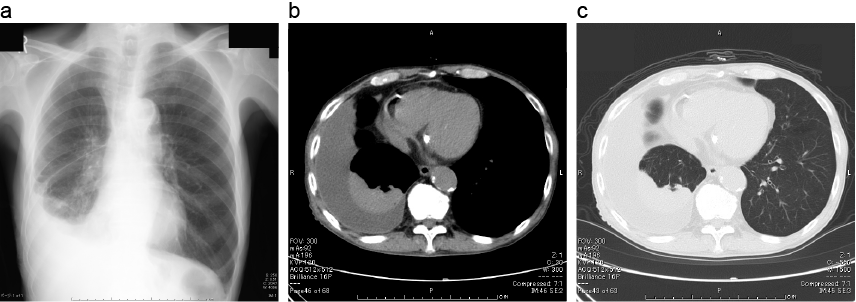

胸水による受動性無気肺 胸部画像

a:胸部単純X線では右肋横隔膜角が鈍であり、右胸水の存在が疑われる。

b、c:胸部単純CTでは、右胸水の貯留と、含気が低下した肺が認められる。明らかな腫瘤など閉塞性無気肺をきたす所見はなく、受動性無気肺と考えられた。